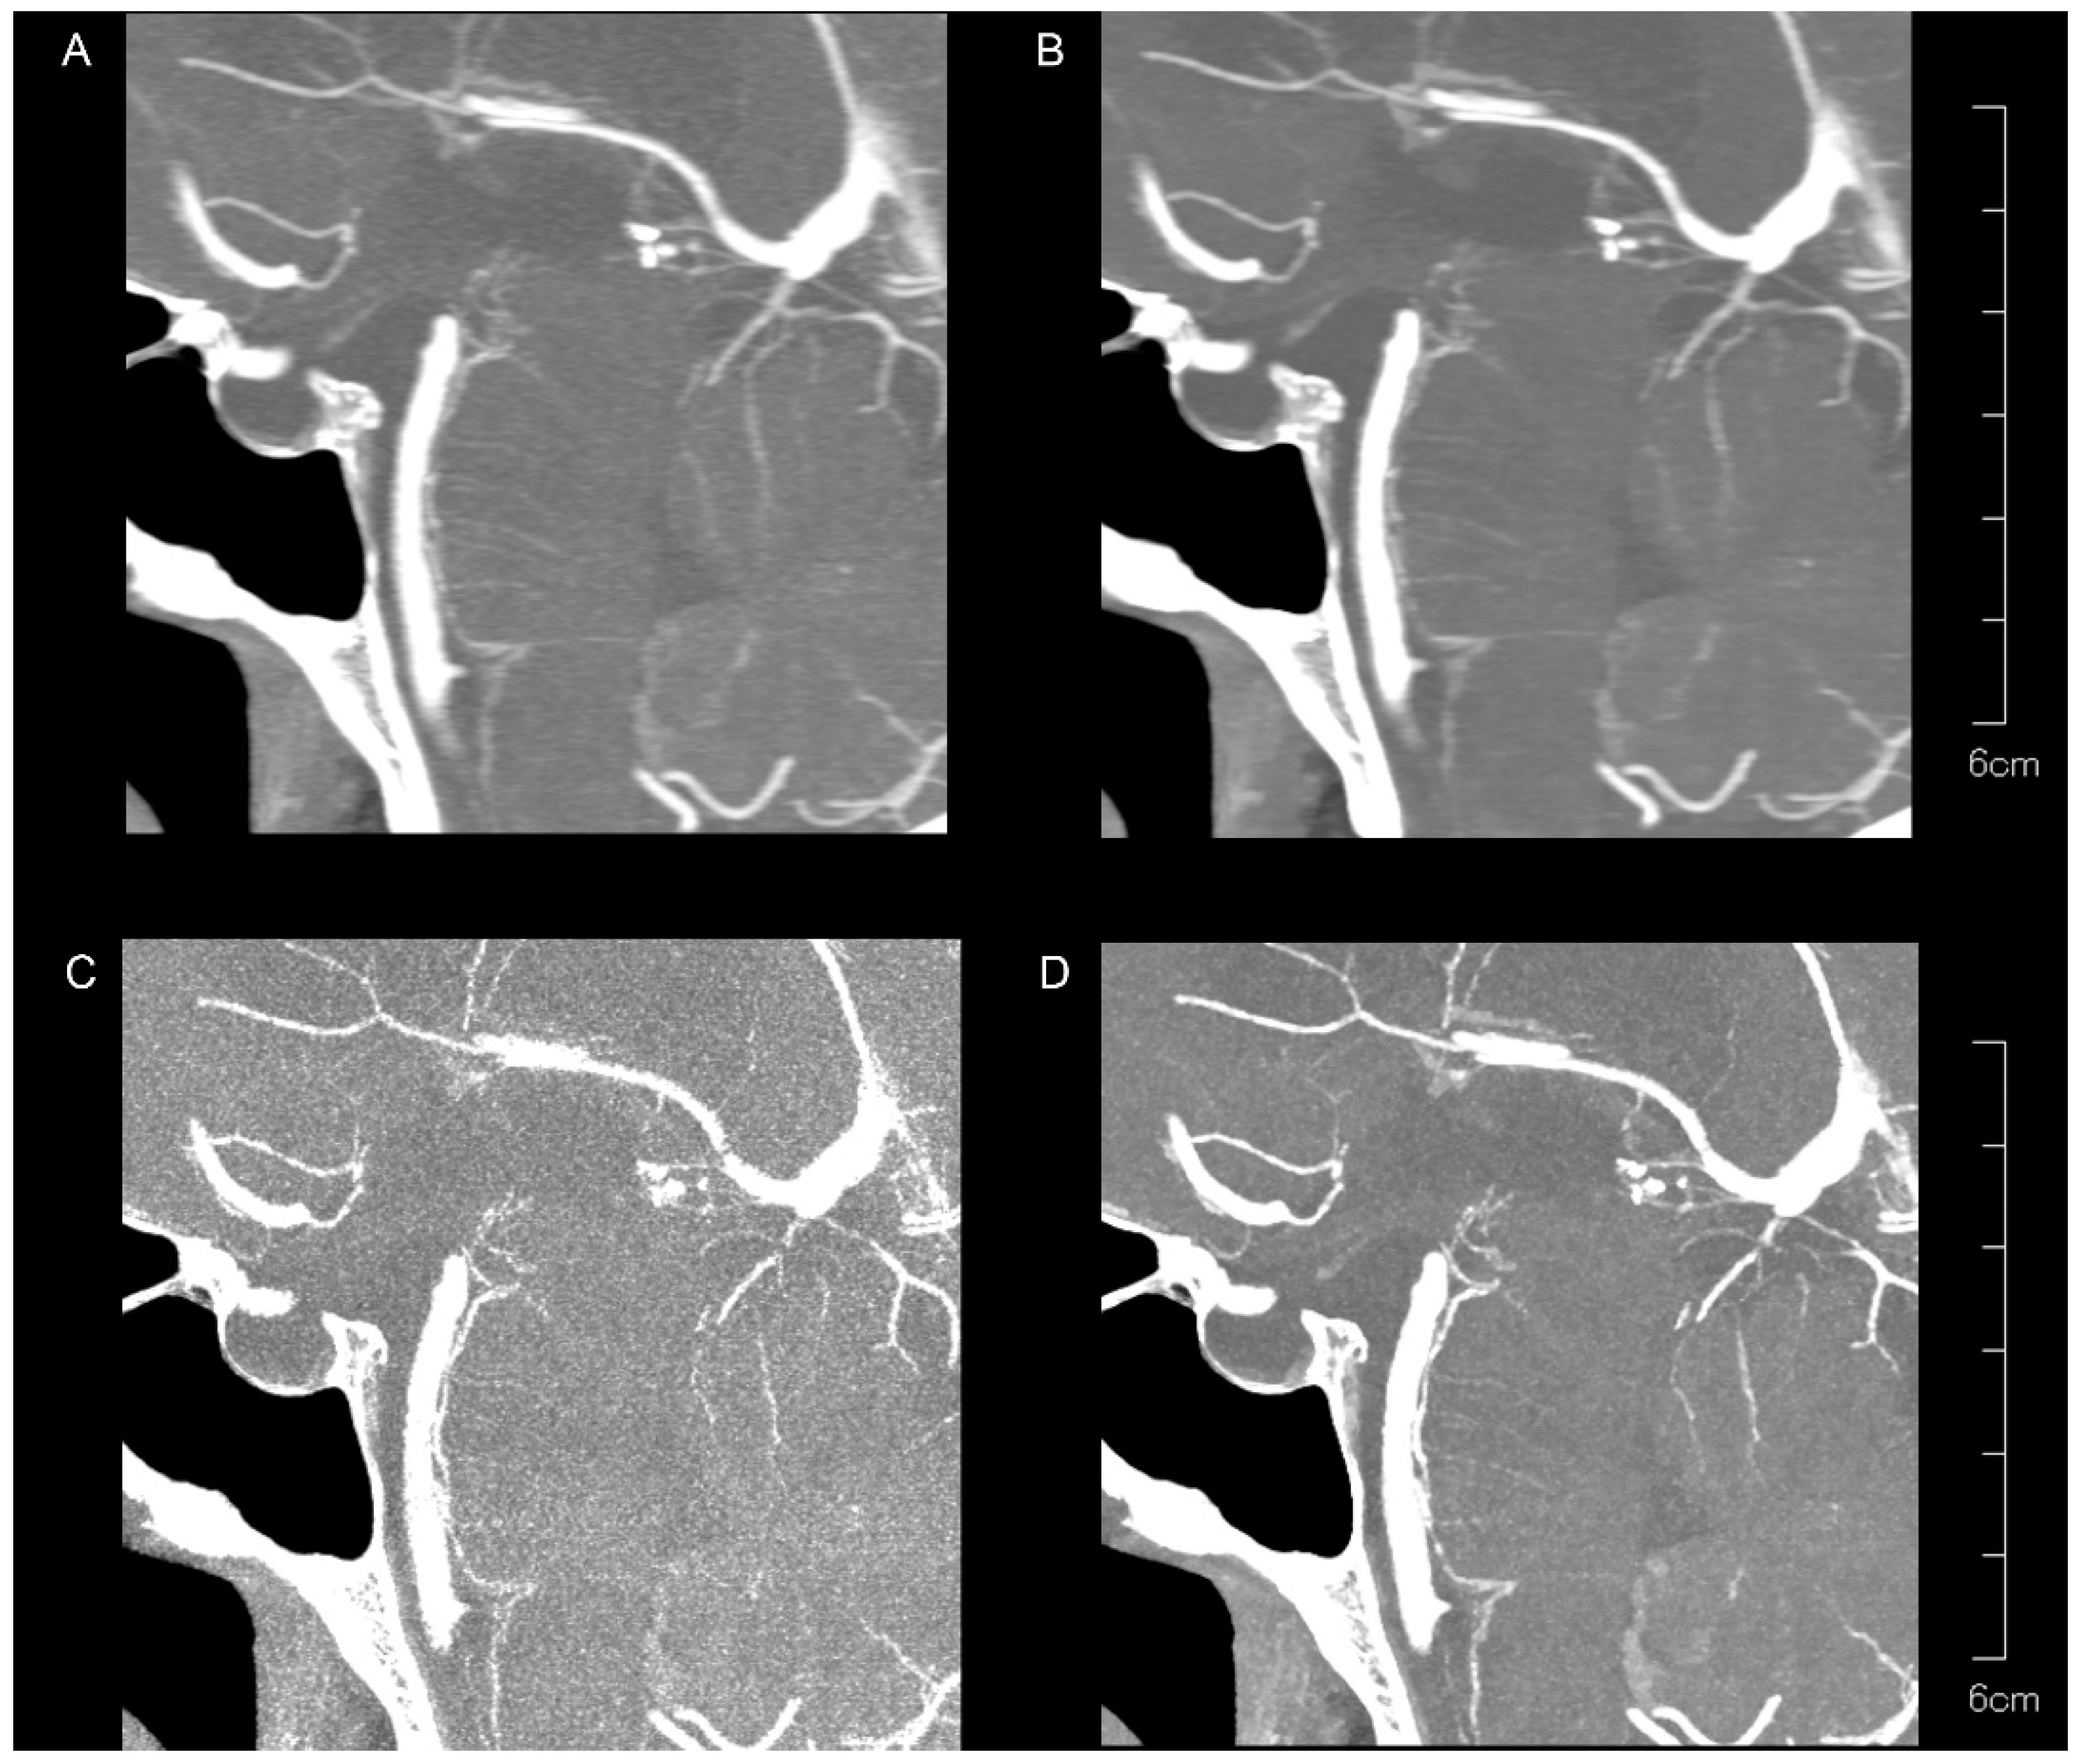

| PA | Kernel Hv40 Without QIR | Kernel Hv40 with QIR | Kernel Hv72 Without QIR | Kernel Hv72 with QIR | p |

| Peripheral visibility | |||||

| Reader 1 | 2 (1–3) | 2 (1–3) | 2 (1–2) | 2 (1–3) | 0.257 |

| Reader 2 | 2 (1–3) | 2 (1–3) | 2 (1–2) | 2 (1–3) | 0.00007 |

| Vessel sharpness | |||||

| Reader 1 | 1 (1–2) | 1 (1–2) | 1 (1–2) | 2 (1–2) | <0.00001 |

| Reader 2 | 1 (1–2) | 1 (1–2) | 2 (1–2) | 2 (1–2) | <0.00001 |

| Noise | |||||

| Reader 1 | 2 (1–2) | 2 (2–2) | 0 (0–0) | 1 (1–2) | <0.00001 |

| Reader 2 | 2 (1–2) | 2 (2–2) | 0 (0–1) | 1 (1–1) | <0.00001 |